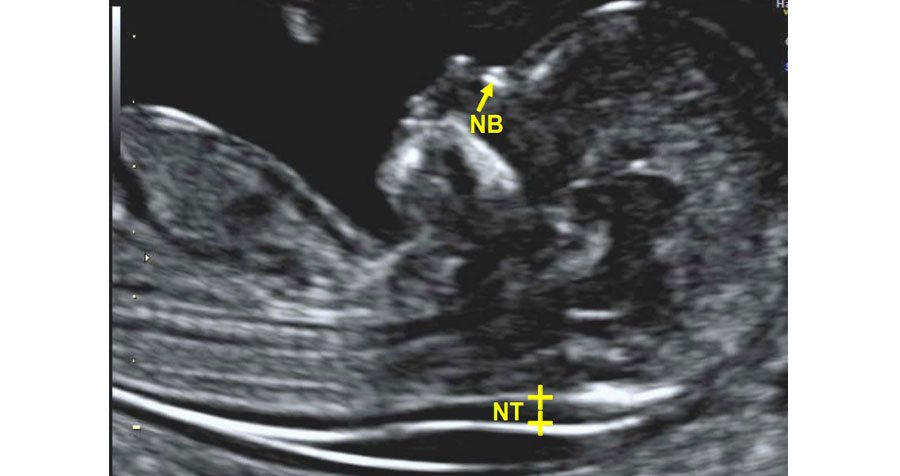

The NT/NB scan, also known as the nuchal translucency (NT) scan or nuchal translucency and nasal bone (NB) scan, is a specialized prenatal ultrasound performed between 11 and 14 weeks of pregnancy. This screening test aims to assess the risk of chromosomal abnormalities, particularly Down syndrome (trisomy 21), and certain other genetic conditions in the fetus. During the scan, the thickness of the fluid-filled space at the back of the baby's neck (nuchal translucency) is measured, and the presence or absence of the nasal bone is evaluated. An increased NT measurement or absence of the nasal bone can be indicative of an elevated risk of chromosomal abnormalities. The NT/NB scan is often combined with maternal blood tests (such as the first-trimester combined screening test) to provide a more comprehensive assessment of the fetus's risk for chromosomal abnormalities. Depending on the results, further diagnostic testing, such as chorionic villus sampling (CVS) or amniocentesis, may be recommended for confirmation. This scan plays a crucial role in early prenatal care, allowing healthcare providers to offer appropriate counseling and management to expecting parents.